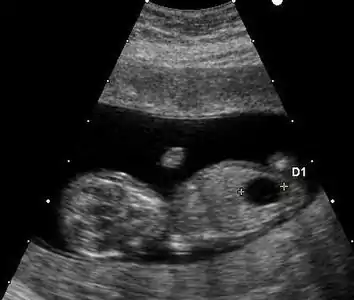

Ultrasound

Ultrasound imaging can be used to screen for Down syndrome. Findings that indicate increased chances when seen at 14 to 24 weeks of gestation include a small or no nasal bone, large ventricles, nuchal fold thickness, and an abnormal right subclavian artery, among others.[94] The presence or absence of many markers is more accurate.[94] Increased fetal nuchal translucency (NT) indicates an increased possibility of Down syndrome picking up 75–80% of cases and being falsely positive in 6%.[95]